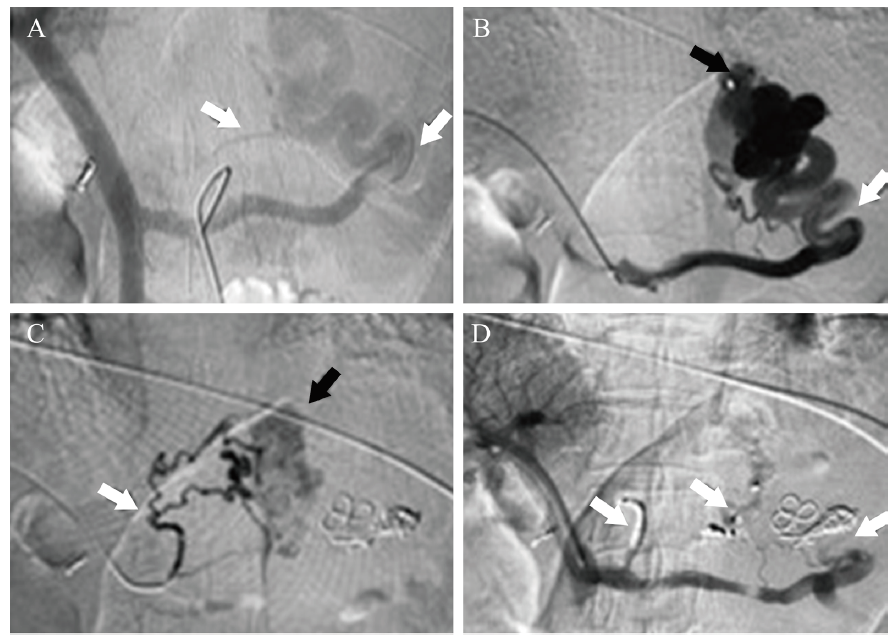

图2 TIPS手术图

注:该例患者即图1患者, 经颈静脉入路建立通道, 黑泥鳅导丝及导管配合下经右侧颈内静脉-无名静脉-上腔静脉-右心房-下腔静脉选入肝右静脉, 导丝引导下更换RUPS100长鞘至肝右静脉, 退出导丝植入穿刺针, 经肝右静脉-肝实质-门静脉右支建立门-体分流道(肝静脉-门静脉通道, 即TIPS分流道);植入加长超硬导丝, 导丝引导下应用球囊导管扩张肝内分流道, 一边撤球囊压力一边往门静脉送入长鞘至门静脉主干, 透视造影下精确测量门静脉入针点至肝静脉入针点距离选用合适支架, 导丝配合下精确释放支架, 治疗后造影, 门静脉、门-体分流道、肝静脉血流通畅, 血液回流至下腔静脉通畅。